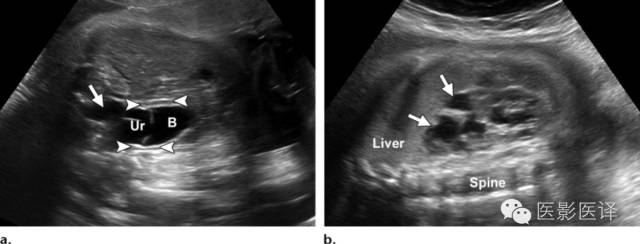

输尿管囊肿是由于输尿管末端扩张而形成。超声表现为位于膀胱内的薄壁、无回声囊性肿块,偶尔会形成假分隔。影像上,如果能看到该囊性肿块是输尿管的直接延伸即可确诊输尿管囊肿(图11)。输尿管囊肿可分为单纯性和异位性。单纯性输尿管囊肿位于膀胱输尿管入口处(膀胱三角区)。异位输尿管囊肿通常与肾脏集合系统重复畸形相关,肾脏上半部分的输尿管插入点位于膀胱三角区的内下方。单纯性或异位性输尿管囊肿可能导致输尿管积水及肾盂积水。巨大的单纯性输尿管囊肿可能会阻塞对侧输尿管口,异位性输尿管囊肿可能导致重复集合系统的输尿管口狭窄。通常,肾盂积水是常规超声检查最早发现的。膀胱部分充盈是诊断输尿管囊肿的理想状态,因为膀胱完全充盈时可能压迫输尿管囊肿,而膀胱不充盈时可能将输尿管囊肿误诊为膀胱本身。一旦诊断了输尿管囊肿,还应仔细检查整个泌尿生殖道,排除是否合并集合系统畸形(图12)。

因为尿液是无回声的,一个内部有回声的肿块不应该被误诊为输尿管囊肿。少数输尿管囊肿位于膀胱外,可能会与腹内其他囊肿相混淆,包括那些卵巢来源的。一般而言,输尿管囊肿是在膀胱内而不是与膀胱相邻,它的大小会随尿流量而变化。然而,卵巢囊肿大小不会变化,通常位于膀胱的旁矢状面上方。

图11.输尿管囊肿及输尿管积水。(a)通过胎儿盆腔的超声斜横断面图像显示膀胱(B)内由输尿管囊肿(Ur)引起的“膀胱内膀胱”的征象。注意由此引起的输尿管积水(箭)。箭头指示脐动脉绕过膀胱,(b)同一胎儿,通过右肾的超声冠状面图像显示明显的肾盏扩张(箭)和被阻塞的上半部分肾皮质变薄。